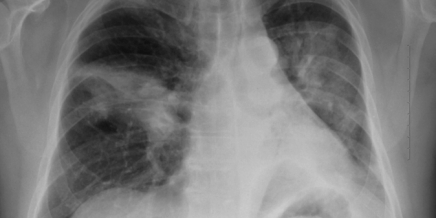

Multiple pulmonale Infiltrate: Diagnose, Therapie und Verlauf

Lernziel Anamnese, Klinik, logische Schritte zur Diagnose, Bildanalyse, Therapie.

Was dieser Kurs von Ihnen verlangt Dyspnoe führt den Patienten zum Arzt. Bildmorpholigische Infiltrate müssen therapiert werden. Der behandelnde Arzt entscheidet, welche weiteren Schritte dann zur eindeutigen Diagnose führen.